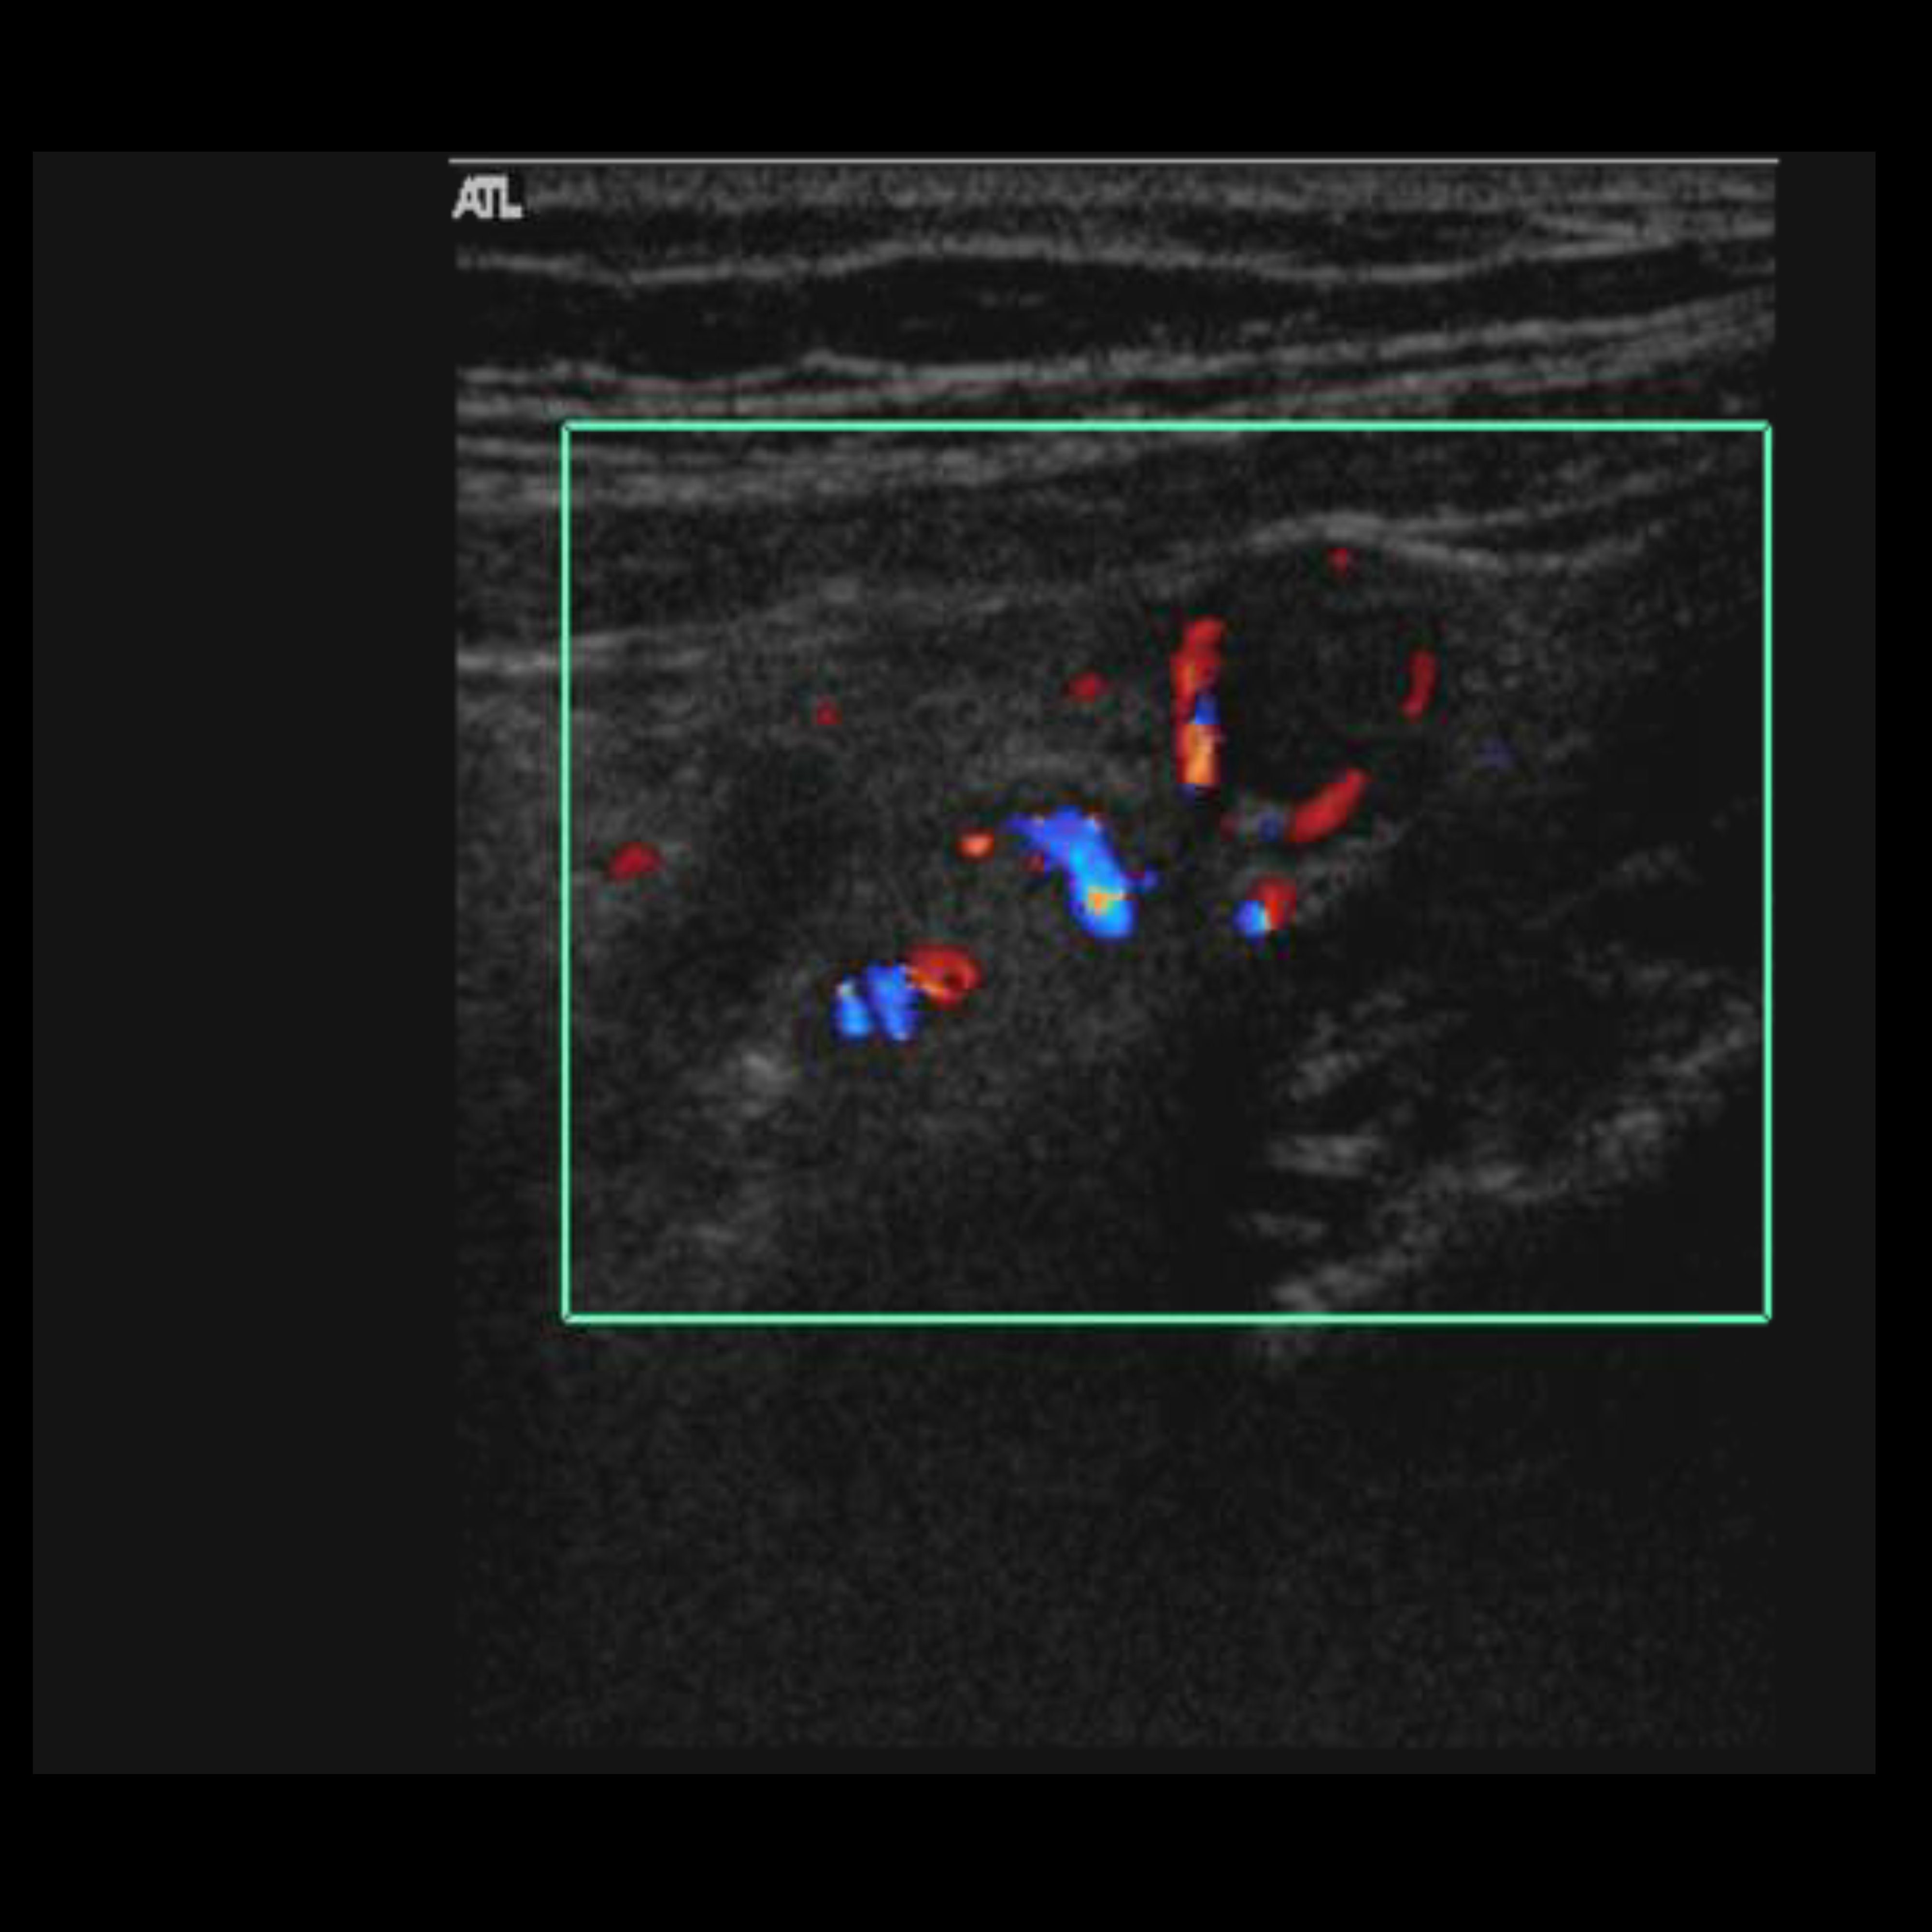

Appendicitis 7

Appendicitis found with hyperemia, free fluid and mural gas found to be perforated on surgery.